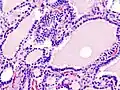

Hyperthyroidism is one of the most common endocrine conditions affecting older domesticated housecats. In the United States, up to 10% of cats over ten years old have hyperthyroidism.[64] The disease has become significantly more common since the first reports of feline hyperthyroidism in the 1970s. The most common cause of hyperthyroidism in cats is the presence of benign tumors called adenomas. 98% of cases are caused by the presence of an adenoma,[65] but the reason these cats develop such tumors continues to be studied.